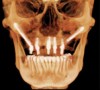

Fig 13. Short implants used to avoid grafting. Fig 13: Occlusal view of a full-arch fixed dental prosthesis supported by five endosseous

implants placed. Fig 14: The left distal implant was tilted to support the left molar unit of the prosthesis. Fig 15: A 6 mm x 5.4 mm implant

was used to support the right molar unit of the prosthesis. The strategic application of nongrafted solutions helped accelerate treatment and

reduce treatment costs.

Figure 13